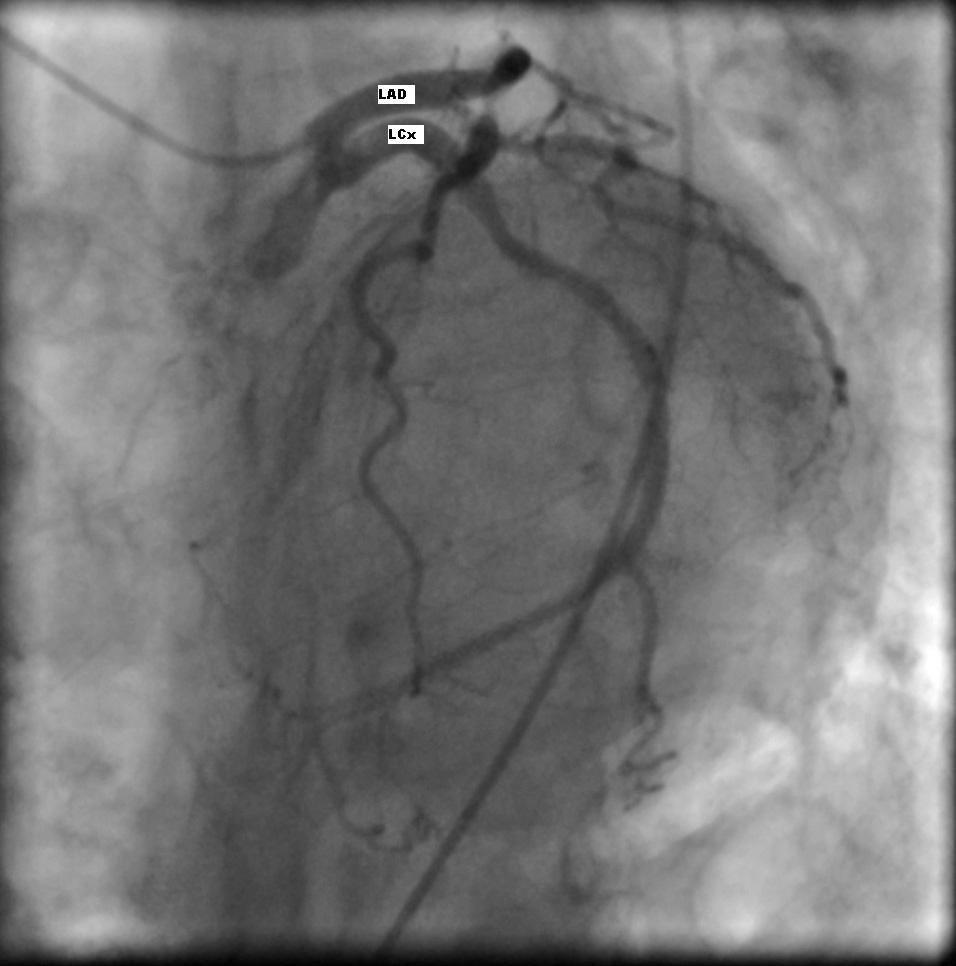

Анатомия коронарных артерий: КТ-изображения